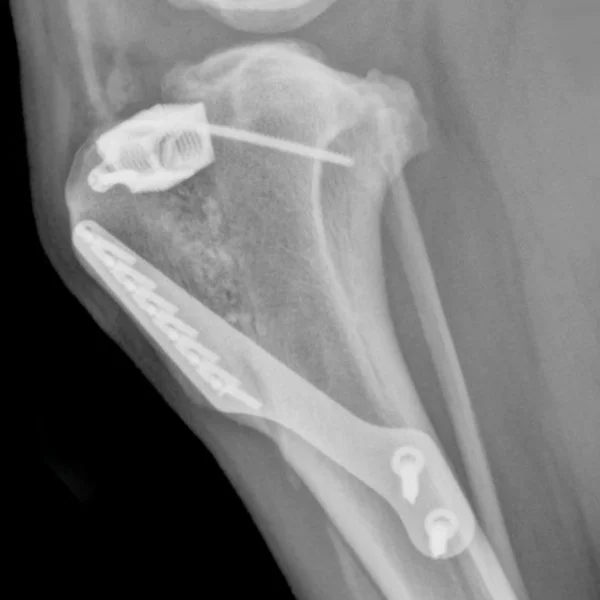

Execution

The TTA involves an osteotomy of the non-weight bearing portion of the tibia. The patellar ligament is aligned perpendicularly to the common tangent of the femorotibial joint, eliminating cranial tibial thrust. This new alignment eliminates the need for the CrCL and results in a stable joint.

• The required advancement of the patellar ligament insertion at the tibial tuberosity is measured from a radiograph of the stifle in extension.

• With a frontal plane osteotomy, the tibial tuberosity is advanced and held in position by:

(1) A cage transferring the compression component of the patellar ligament force from the tuberosity to the proximal tibia

(2) A tension band plate transferring the patellar ligament force to the proximal diaphysis of the tibia

• The open osteotomy, distal to the cage, is grafted with autologous cancellous bone or other graft material such as allograft or hydroxyapatite (HA) to accelerate healing.